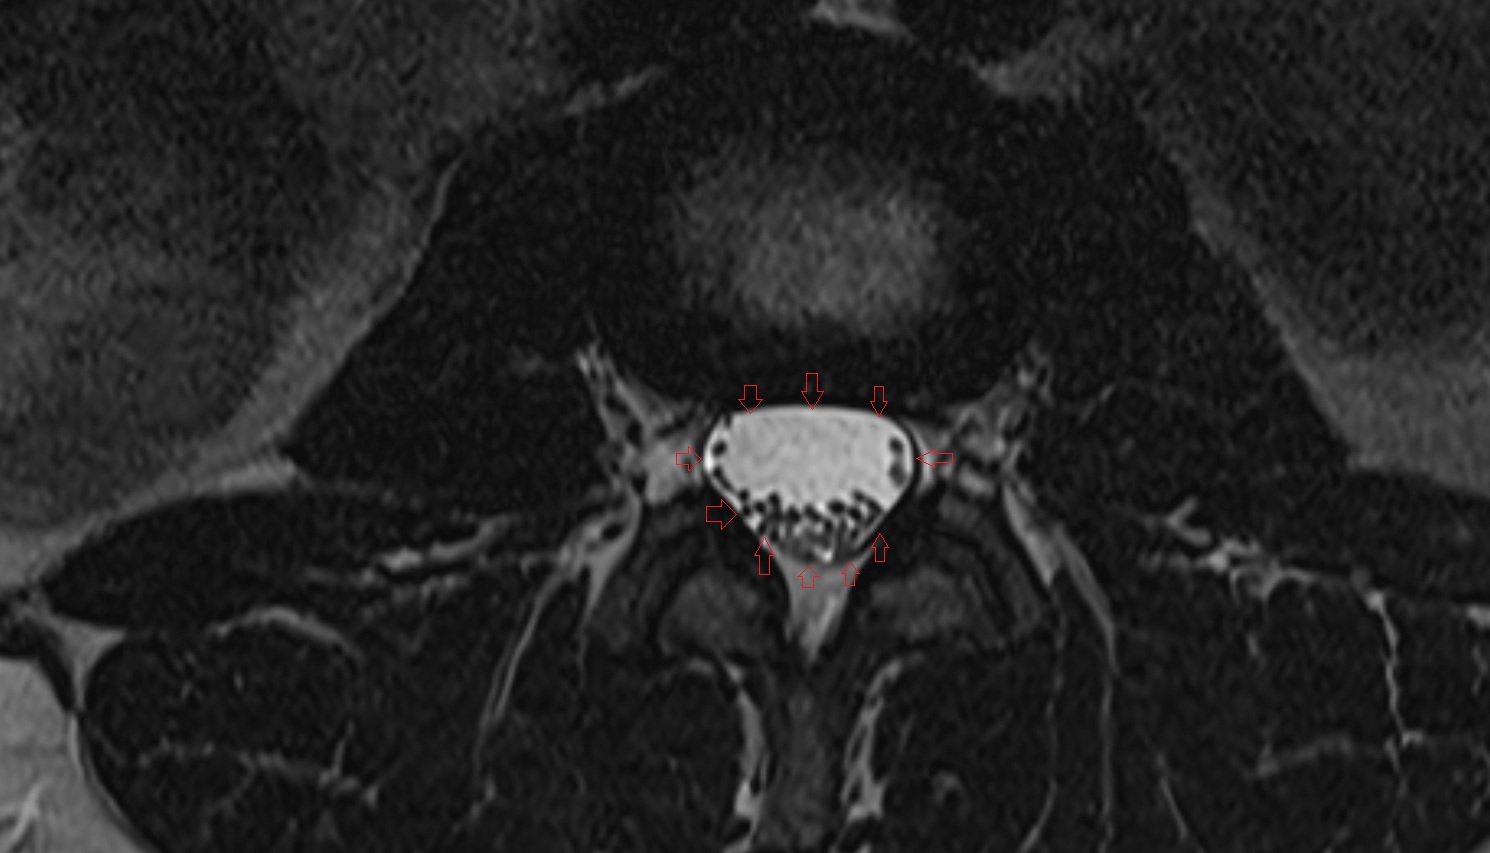

- Cauda equina

- Traversing nerve root of spinal nerve

- Exiting nerve root of spinal nerve

- Spinal dura mater

- Spinal epidural space

- Dorsal traversing nerve root

- Ventral traversing nerve root

- Dorsal exiting nerve root

- Ventral exiting nerve root

- Dorsal root ganglion of spinal nerve